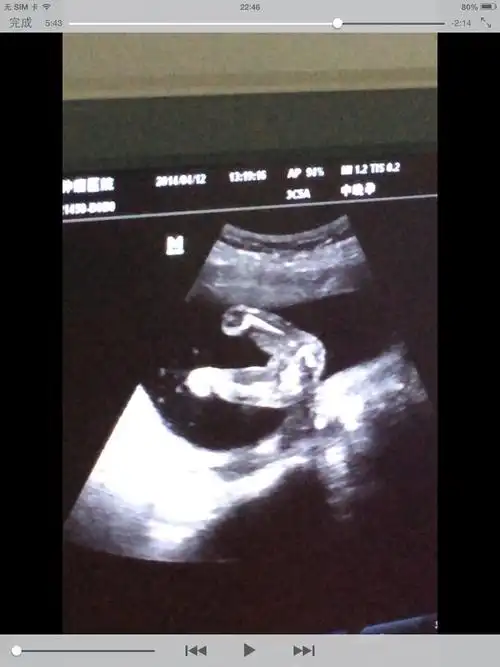

男女胎儿b超发育全过程高清图

【怀孕几个月可以看男女】怀孕几个月可以看出胎儿性别_几周可以看出

b超单上3个数据,或许暗示胎儿性别"秘密",看不懂的孕妈好可惜